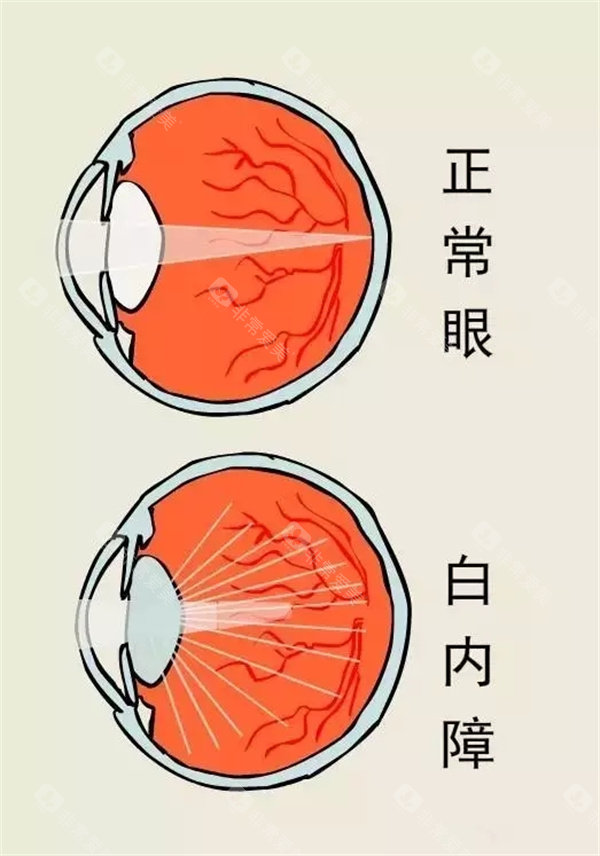

基于第七次国境内人口普查数据,呼市常住人口344.61万人,65岁以上老年群体占比达13.83%,总量约50万人。而中华医学组织眼科学分会的统计显示,我国60岁以上人群白内障发病率约80%,庞大的患病基数让政策延续成为民生刚需。

医学层面,申请者需经专科诊断确诊为白内障,且裸眼视力≤0.3或矫正视力<0.5,这一标准是判断手术必要性的核心依据。同时需排除相关禁忌症,例如活动性眼部感染、未控制的全身性疾病等。